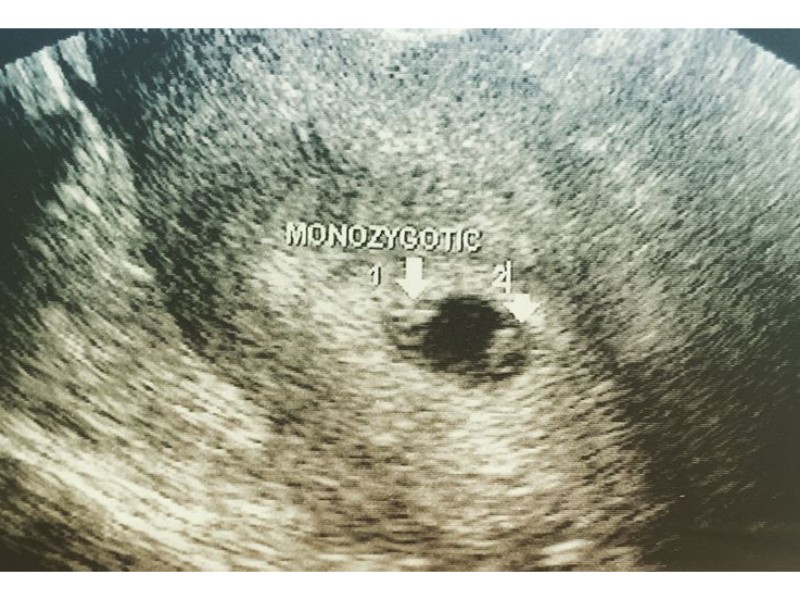

Iniciando el embarazo

Source: www.reproduccionasistida.org

Hafta hafta gebelik rehberi 13. Bebeğin gözleri daha önce birbirinden. Hafta anne karnında bebek gelişimi ultrason görüntüleri.